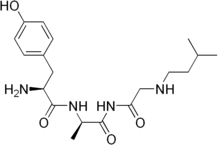

Opioid peptides

Enkephalins

Structures

| Enkephalins | ||||

|---|---|---|---|---|

DAMGO DAMGO |

||||

Propeptides

Others / unknown

- Adrenorphin

- Amidorphin

- Biphalin

- Casokefamide

- Casomorphins

- Cytochrophin-4

- DALDA (Tyr-D-Arg-Phe-Lys-NH2)

- Deltorphin I

- Deltorphin II

- Deprolorphin

- Dermorphin

- DPDPE

- Frakefamide

- Gliadorphin

- Gluten exorphins

- Hemorphin-4

- Metkefamide

- Morphiceptin

- Nociceptin

- Octreotide

- Opiorphin

- Rubiscolin

- Soymorphins

- Spinorphin

- TRIMU 5

- Tynorphin

- Valorphin

- Zyklophin

Structures

| Other or unknown opioid peptides | ||||

|---|---|---|---|---|

Adrenorphin Adrenorphin |

Amidorphin Amidorphin |

Casomorphin Casomorphin |

DALDA DALDA |

|

DPDPE DPDPE |

Endomorphin-1 Endomorphin-1 Endomorphin-2 Endomorphin-2 |

Gliadorphin Gliadorphin |

Morphiceptin Morphiceptin | |

Nociceptin Nociceptin |

Octreotide Octreotide |

Opiorphin Opiorphin |

Rubiscolin Rubiscolin |

TRIMU 5 TRIMU 5 |

Others